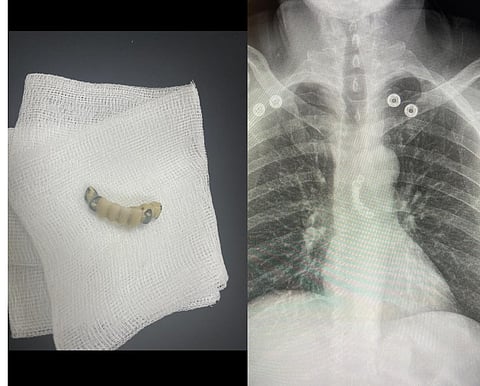

وفي التفاصيل، حضر المريض إلى قسم الطوارئ بالمستشفى الرئيسي برفقة ذويه بعد أن ابتلع طقم الأسنان الخاص به بالخطأ، وكان يُعاني من آلام شديدة في الصدر وعدم القدرة على البلع، وبعد عمل الأشعة والفحوصات الطبية اللازمة التي أظهرت وجود طقم الأسنان في منتصف المريء.

وعلى الفور تم استدعاء الفريق الطبي من الأقسام المختلفة للتعامل الفوري مع الحالة، ونجح الفريق باستخراج الطقم عن طريق عمل منظار الجهاز الهضمي العلوي، وتمت متابعة الحالة حتى استقرارها وغادر المستشفى بصحة جيدة .